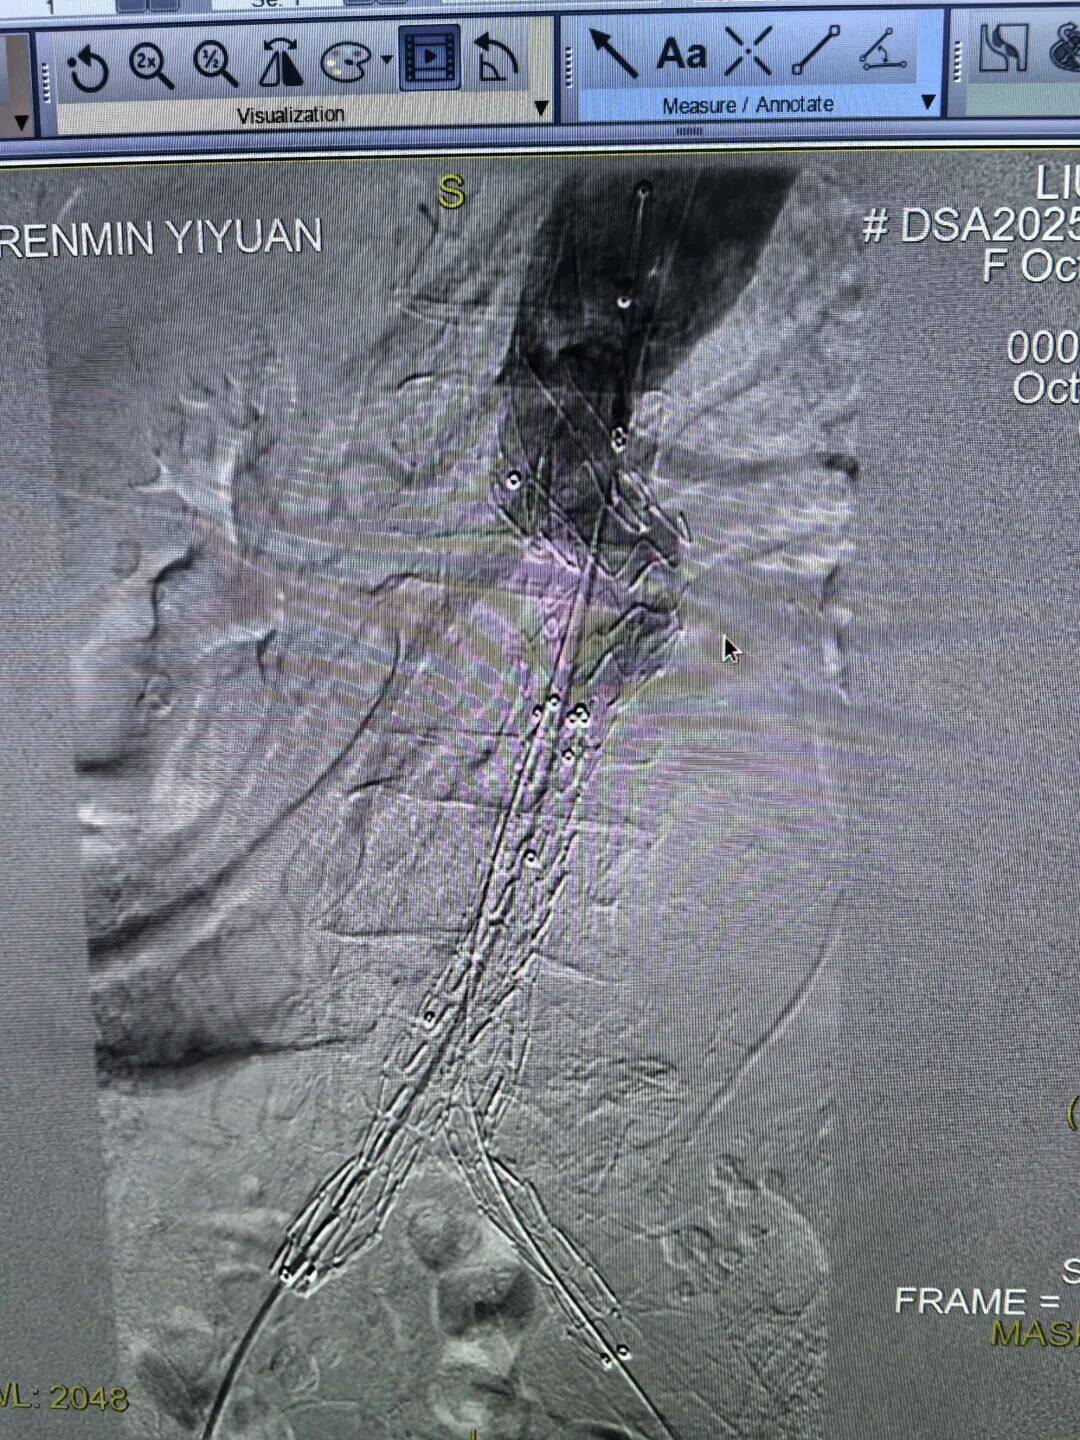

经过专家团队的全面评估和审慎决策,认为唯有行腹主动脉瘤腔内修复术(EVAR)才有一线生机。这是一种微创介入手术,仅需在双侧大腿根部切开约2厘米的小切口,通过股动脉将覆膜支架系统精准输送到动脉瘤部位,像搭桥一样在血管内建立起一道坚固的“屏障”,隔绝破裂的瘤腔,从而达到止血和治愈的目的。

尽管手术方案最优,但患者高龄、血管条件差、耐受能力低,术中任何一个环节出现闪失都可能导致失败。医护团队凭借精湛的技术和丰富的经验,成功将覆膜支架精准释放到位。造影显示,支架定位完美,动脉瘤被完全隔绝,活动性出血瞬间停止,手术取得了决定性成功!